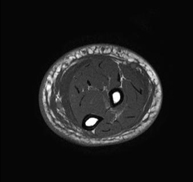

Diagnòstic per la Imatge

Ressonància Magnètica

Múscul – esquelètic

RM d'Avantbraç

RM d'AvantbraçExploració per a l'estudi de lesions en els tendons, els músculs i els nervis perifèrics. La durada aproximada és de 18 minuts. No utilitza radiació ionitzant.